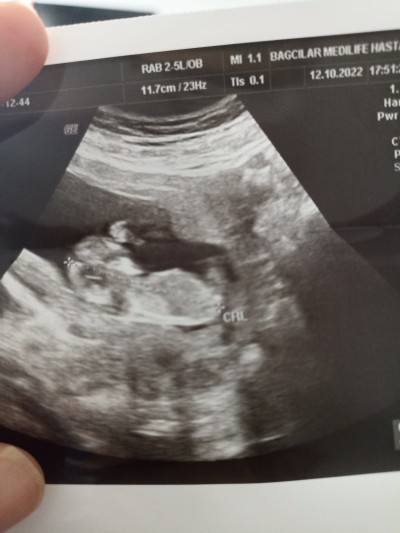

yan durduğu için birşey diyemedi ama duruşundan şeklinden belki anlayıp yorum yapabilen varsa diye paylaşmak istedim tabiki önceliğimiz sağlıklı olsun da fark etmez kızımı bu haftada öğrendiğim için bugün bunuda öğrenirim ddm kndimi çok hazırlamıştım o yüzden merakımı burdan blki gideririm dye paylasiyorum

Gebelik haftası 12